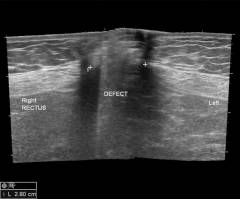

| УЗИ при пупочной грыже | Ультразвуковое исследование позволяет получить информацию о: * размере грыжевого выпячивания; * органе в грыжевом мешке; * наличии и количестве спаек. | УЗИ проводится стандартным способом: пациент ложится на спину, на область пупка наносится гель, и исследование выполняется с помощью ультразвукового датчика. |

| УЗИ при пупочной грыже | Ультразвуковое исследование предоставляет данные о пупочной грыже: * размеры выпячивания; * органы в грыжевом мешке; * наличие и количество спаек. | УЗИ выполняется стандартно: пациент ложится на спину, на кожу в области пупка наносится гель, и исследование проводится ультразвуковым датчиком. |